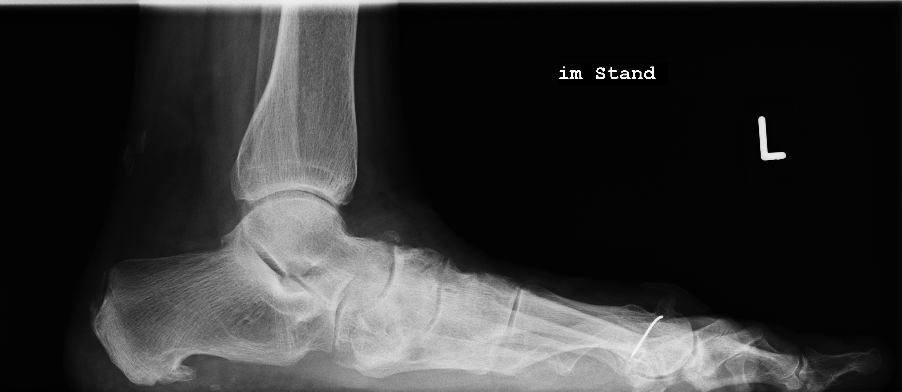

Knick-/Senkfuß des Erwachsenen

Der erworbene Knick-/Senkfuß kann zu unterschiedlichsten Beschwerden führen, was eine differenzierte Herangehensweise des behandelnden Arztes erfordert. Häufig kommt es als Folge auch zu Fehlstellungen der Zehen, was dann ggf. ebenfalls eine Korrektur erfordert. Nur im Anfangsstadium kann man die Beschwerden ohne Operation behandeln, ansonsten sind gelenkerhaltende Eingriffe (Osteotomien) oder gelenkstabilisierende Eingriffe (Arthrodesen) möglich. Letztere finden bei Arthrose, aber auch bei ausgeprägten Fehlstellungen Anwendung. Unabhängig vom OP-Verfahren ist in manchen Fällen eine Verlängerung der Wadenmuskulatur erforderlich.

Die Verschiebung der Ferse nach innen (Calcaneusmedialisierung) führt zur korrekten Lastaufnahme und verbessert die Zugrichtung der Achillessehne. In der Regel sind weitere Maßnahmen wie Verstärkung von Sehnen oder Achskorrektur der Fußinnenseite notwendig. Sollten weitere Beschwerden wie Zehenballen oder Krallenzehen bestehen, wird dieses ebenfalls begradigt.

Aufrichtung durch Stabilisierung

Die Stabilisierung des unteren Sprunggelenkes (Arthrodese) ist eine effektive Methode zur Korrektur des fortgeschrittenen Knick-/Senkfußes, wenn hier bereits als Folge der Fehlstellung Arthrose aufgetreten ist. Dieser Eingriff wird ebenfalls oft mit weiteren Maßnahmen der Fußinnenseite kombiniert. Einige Monate nach der Operation ist in der Regel von außen am Gangbild nicht zu erkennen, dass ein Fußgelenk versteift wurde.